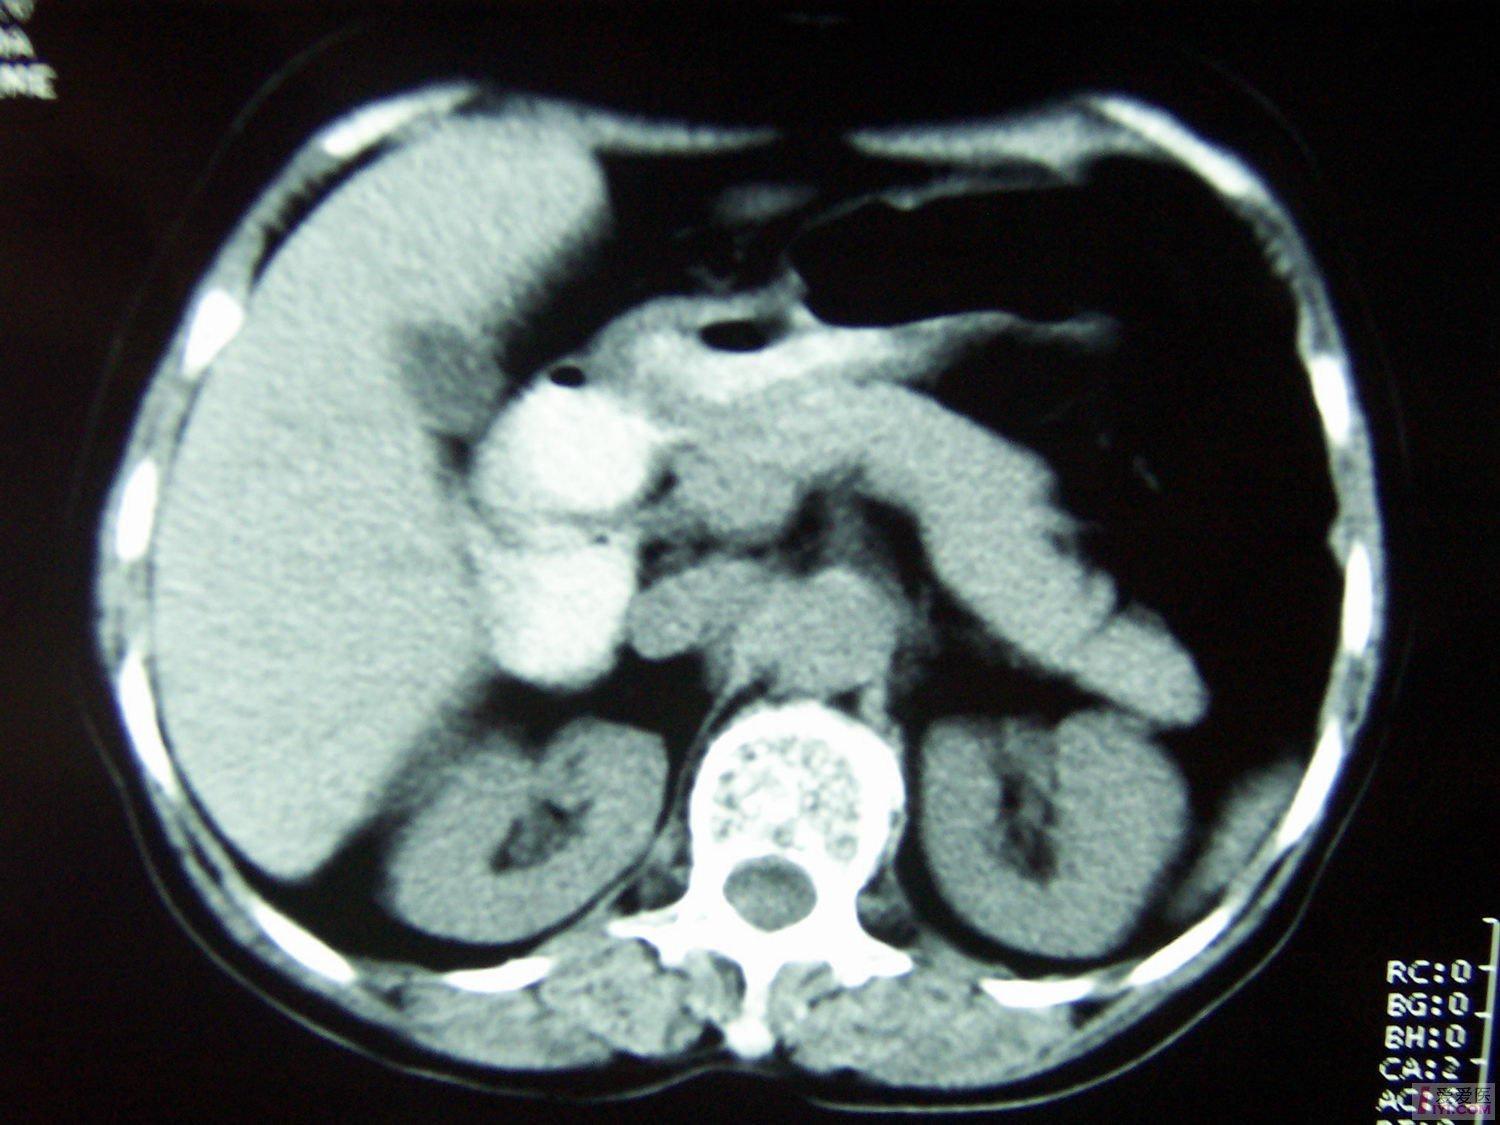

肝癌片子图

肝癌片子图,肝癌诊断书真实图片

【讨论】神奇的片子!肝癌化疗有这么好的疗效吗?请高手赐教!

肝癌ct片图片图解

肝癌ct图片